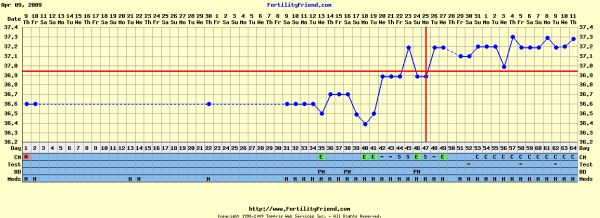

Anna: szerintem volt pé-d, 1-2 nap múlva kapsz is vonalat